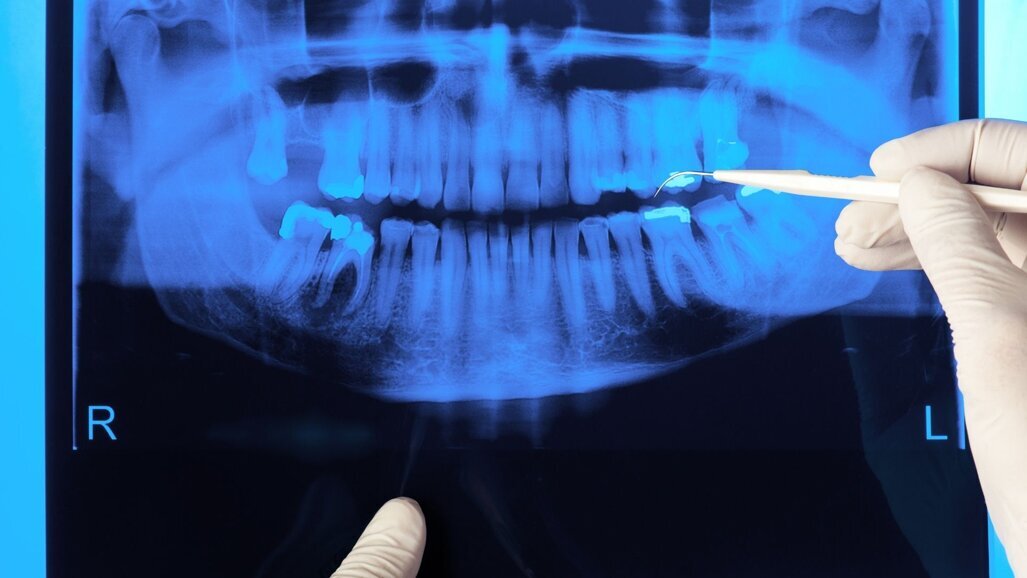

DEN HAAG – De Autoriteit Nucleaire Veiligheid en Stralingsbescherming (ANVS) is half maart gestart met inspecties bij tandartspraktijken, omdat uit recent onderzoek van de ANVS blijkt dat 15 procent van de praktijken geen vergunning of registratie voor een röntgenapparaat heeft. Deze vergunning is nodig sinds de nieuwe regelgeving voor stralingsbescherming uit 2018. Sinds deze nieuwe regelgeving – gebaseerd op Europese richtlijnen – is onder meer registratie van röntgentoestellen en een vergunning voor CT-scanners verplicht.

Inspecteurs van de ANVS gaan fysiek vijftien prakijken bezoeken die op papier niet lijken te voldoen aan de regels voor vergunning of registratie. Naast de vergunning of registraties controleren ze de deskundigheid om te werken met straling, kijken ze of medewerkers van de praktijk zich aan de veiligheidsvoorschriften houden en checken ze de kwaliteit van de administratie. Na de zomer verwacht de organisatie de resultaten te presenteren.

Door eerdere inspecties en communicatie is de naleving toegenomen, maar uiteindelijk moeten alle praktijken voldoen aan de wet. Bij eerdere inspecties in 2019 bleek dat van de 500 geïnspecteerde tandartspraktijken rond de 30 procent nog geen geldige registratie of vergunning had. 35 procent had de deskundigheid niet goed op orde. Het is met de nieuwe regelgeving bijvoorbeeld verplicht om advies in te winnen van een stralingsbeschermingsdeskundige.

Als er sprake is van een overtreding in een praktijk, volgt een herinspectie en kan de ANVS een waarschuwing geven of op een strafrechtelijke manier optreden. Zo kan de organisatie bijvoorbeeld alle handelingen met het röntgenapparaat stilleggen.